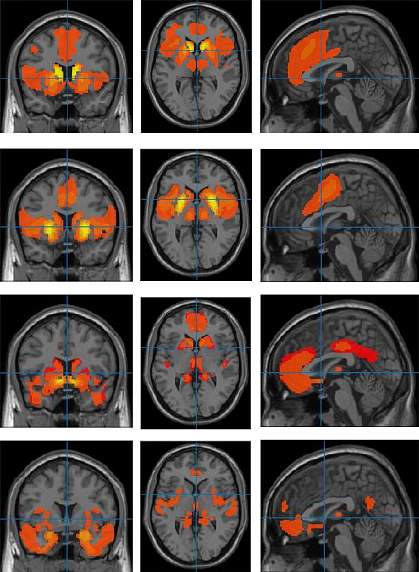

An NIH research team re-analyzed fMRI images collected in six previous studies. Altogether, those studies had obtained fMRI images from more than 1,696 youths with ADHD, aged 6 to 18, as well as almost 7,000 without the condition. In addition to using a large number of images, the researchers strictly defined the brain areas being measured. This allowed for more accurate comparisons between individual fMRI scans. Results were published March 13, 2024, in the American Journal of Psychiatry.

The team found that the brains of youth with ADHD had more activity between several subcortical regions and the frontal cortex than those in youth without the condition. The brains of youth with ADHD also showed greater connection between the frontal cortex and part of the brain called the amygdala. The amygdala helps process emotions and had been suspected to play a role in ADHD.

These results were seen regardless of children’s sex, age, race or ethnicity, socioeconomic status, or estimated intelligence. The differences in brain connectivity also didn’t appear to be affected by the presence or absence of other mental health problems, such as anxiety or depression. However, the differences found by the researchers were small and likely capture only part of the processes involved in ADHD.